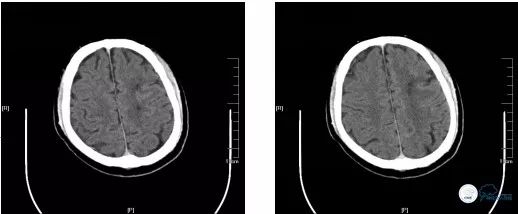

再次经球囊Guiding导管动脉推入4ml替罗非班。遂再次沿Transend微导丝送入自膨式 Enterprise(4.5mm*28mm)支架,准确定位后缓慢释放,再次手推造影提示支架贴壁欠佳,再次以同样方式送入Tazuna球囊(2.5*20mm)扩张支架后,造影提示:左颈内动脉管壁较前改善,前向血流较前改善(TICI分级2b级),无急性血管闭塞征象(图21)

术后患者无不适主诉,血压130/80mmHg,心率72次/分,神经系统查体较前无明显变化,术后即刻行头CT检查未见出血(图21),安返病房。

术后头颅CT(2018-06-14):左侧半卵圆中心散在陈旧性梗死灶(图22)